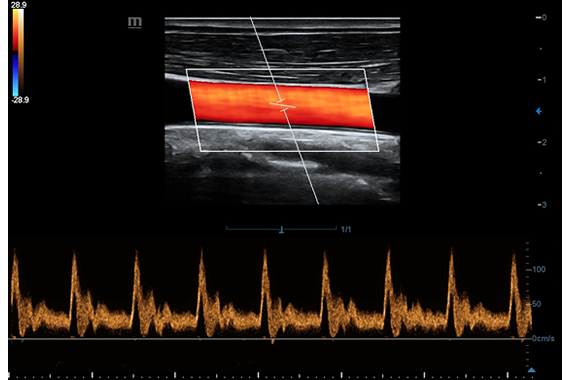

• Поддержка режимов сканирования B/M/Цветовой доплер CDI/Цветной M/Энергетический доплер PD/Направленный энергетический доплер Dir.PD.

• Импульсно-волновой доплер, включая режим высокой частоты повторения импульсов HPRF.

• HR Flow - режим отображения кровотока с высоким временным и пространственным разрешением для точной и однородной визуализации сосудов, в том числе самых мелких.

Цветовой допплер:

Импульсно-волновой допплер:

• HR Flow - режим отображения кровотока с высоким временным и пространственным разрешением для точной и однородной визуализации сосудов, в том числе самых мелких